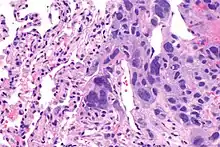

The ovarian yolk sac tumors, also known as endodermal sinus tumors, are accountable for approximately 15.5% of all OGCTs.[11] They have been observed in women particularly in their early ages, and rarely after 40 years of age.[12] The critical pathologic features are a smooth external surface and capsular tears due to their rapid rate of growth. A study consisting of 71 individual cases of ovarian yolk sac tumor provides evidence to the proliferation of the tumor. In one of the cases, the pelvic examination revealed normal activity until a 9 cm and 12 cm sized tumor was discovered 4 weeks later.[12] In another case, a 23 cm tumor was discovered in a pregnant woman who was monitored regularly and had normal findings until oophorectomy became essential.[12] Histologically, these tumors are characterized by mixed solid and cystic components.[1] The mixed solid components are characterized by a soft gray to yellow solid components accompanied with significant hemorrhage and necrosis. The cysts are approximately 2 cm in diameter and populated throughout the tissue which results in giving the neoplasm a ‘honeycombed appearance’.[1]